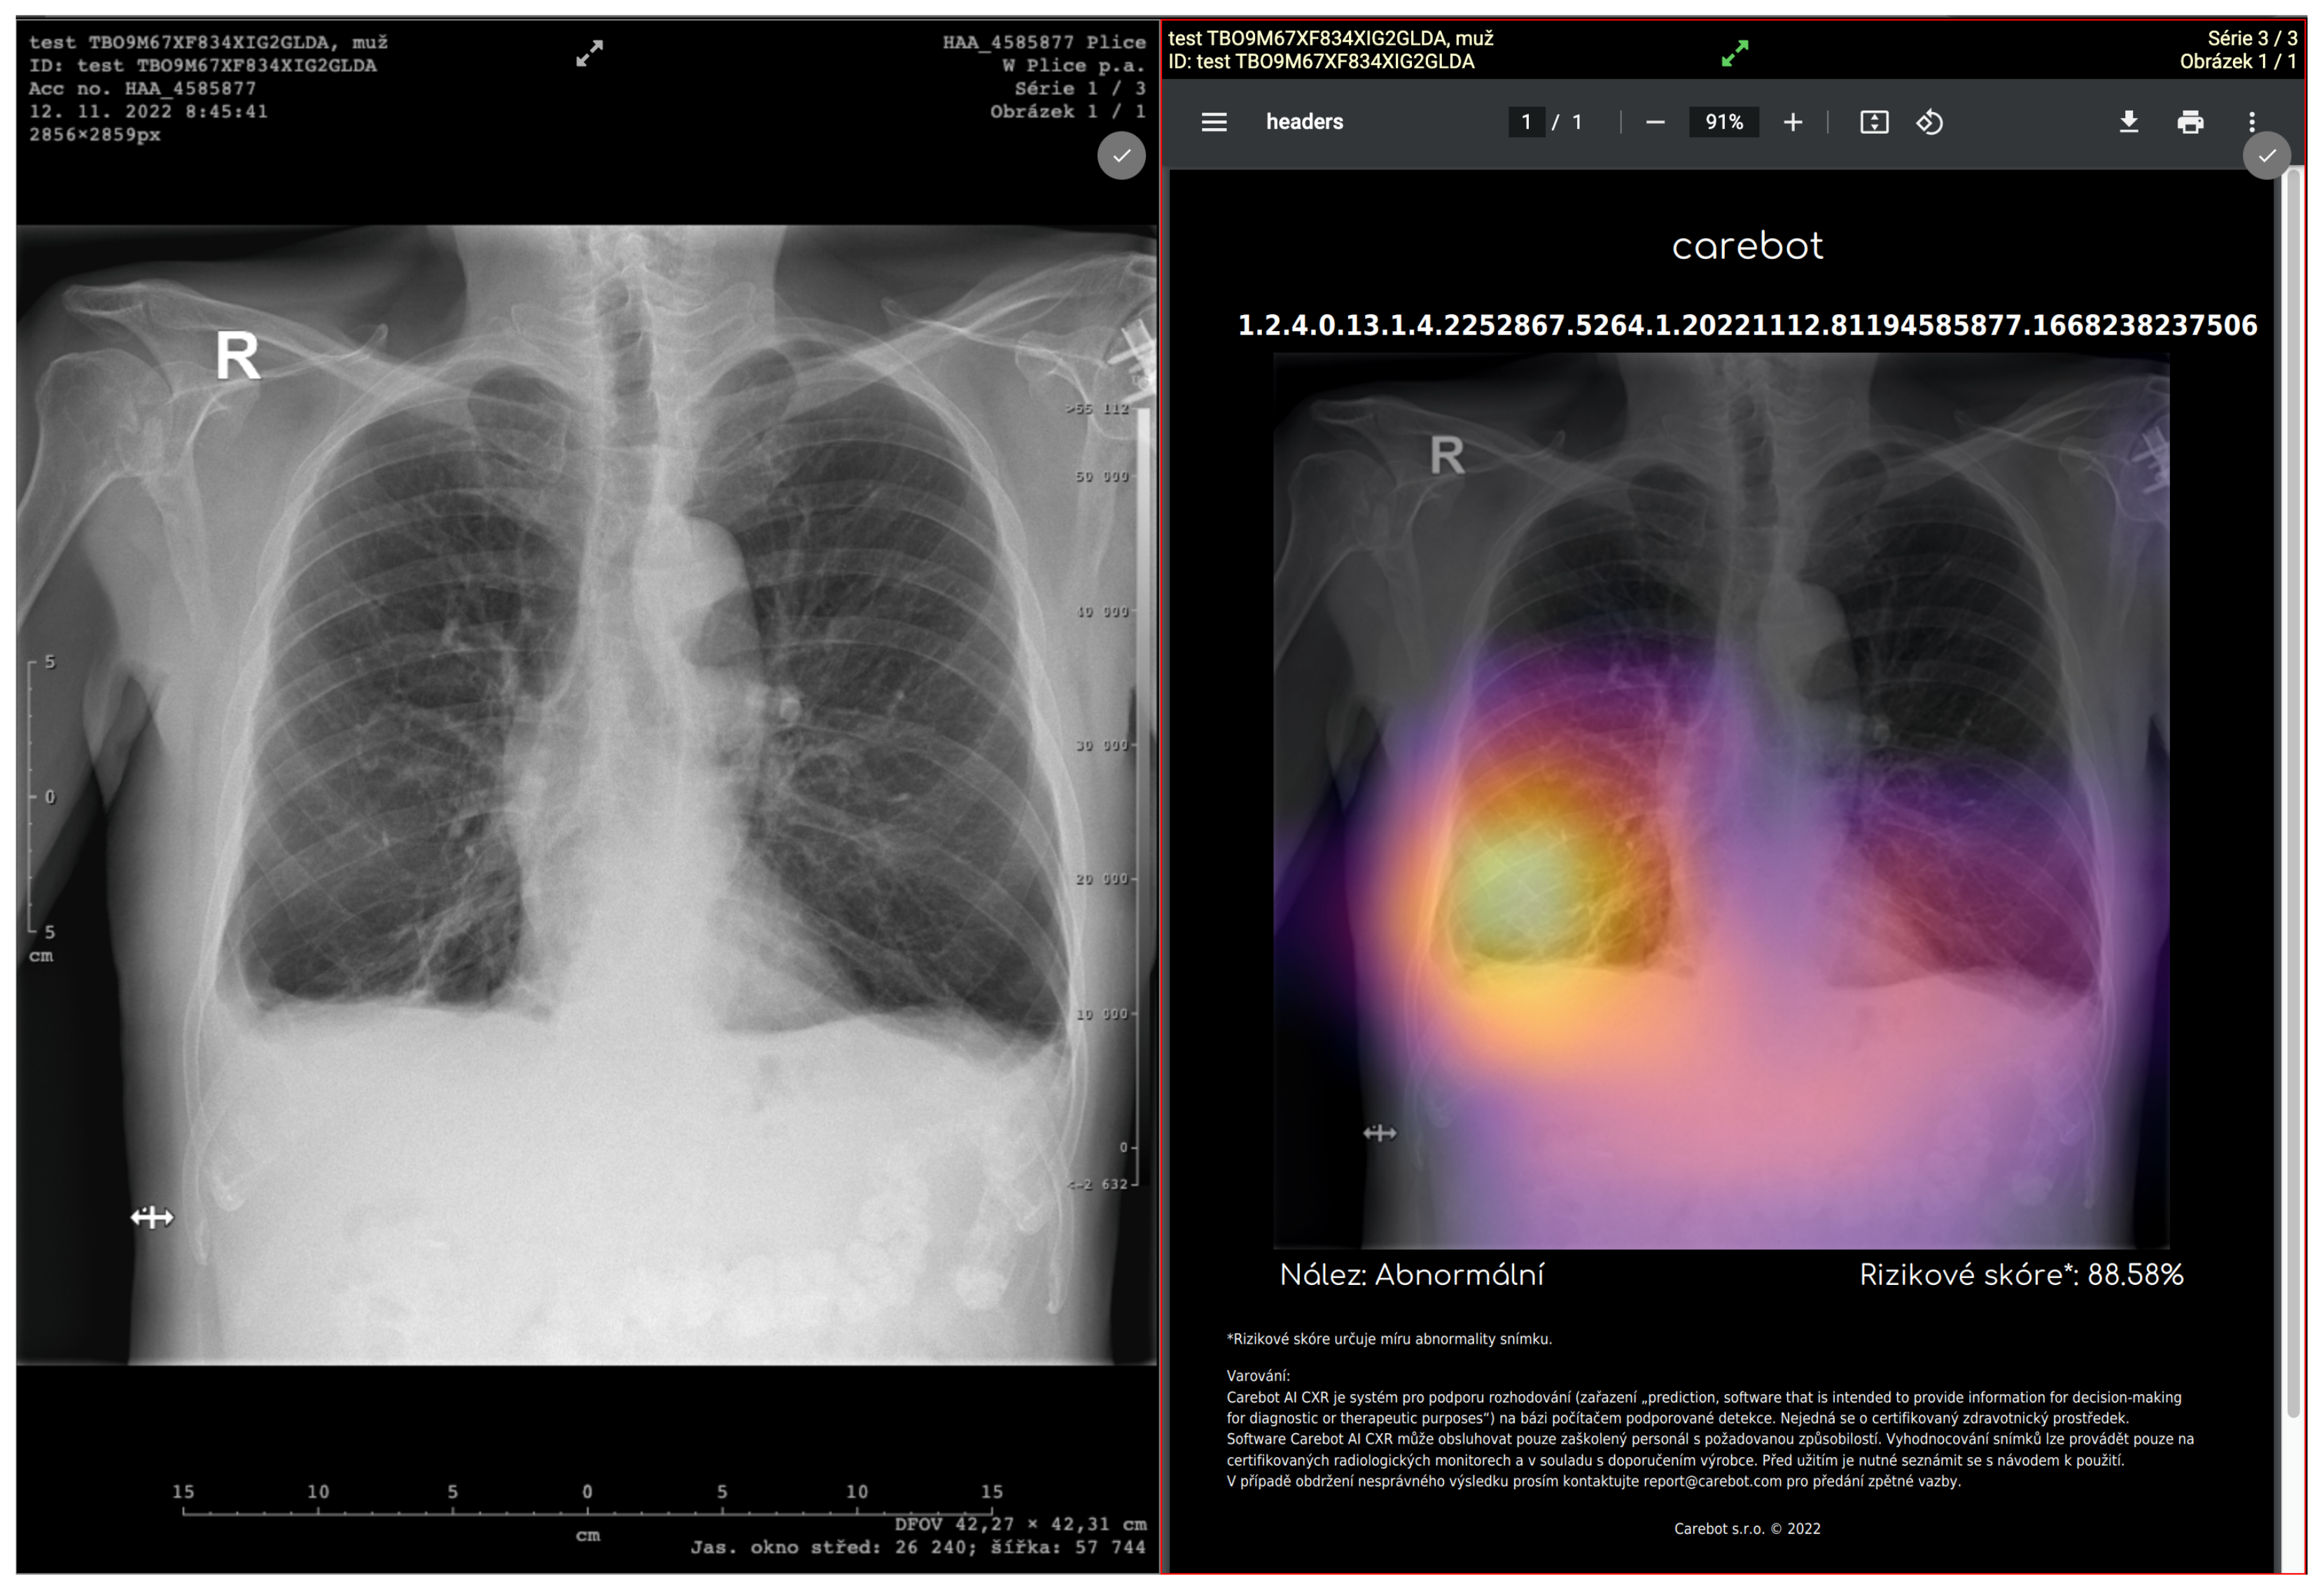

The purpose of our study is to provide evidence that the investigated pre-certification medical device (shown in Figure 3) meets the requirements in accordance with its intended use. Given this, a retrospective study was performed to evaluate the clinical effectiveness on prospectively collected CXRs. The evaluation of DLAD performance compared to that of radiologists in standard clinical practice was set as the primary endpoint of the study. (The methodology and statistical evaluation was designed in collaboration with the Institute of Biostatistics and Analysis, Ltd.)

Figure 3.

User interface of DLAD software implemented in PACS (CloudPACS by OR-CZ).